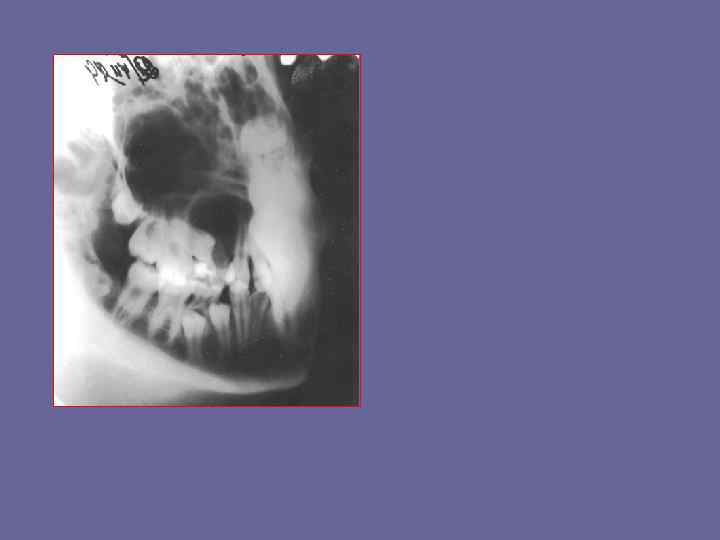

Опишите рентгенограмму

По мере рост кисты могут распространяться одновременно в сторону полости носа и в сторону верхнечелюстной пазухи

Кисты могут вызывать конвергенцию коронок зубов. В связи с меньшим сопротивлением давлению в альвеолярном отростке верхней челюсти, кисты этой локализации увеличиваются во всех направлениях, что приводит к образованию полости неправильной формы.

Кисты могут вызывать нарушение смены зубов